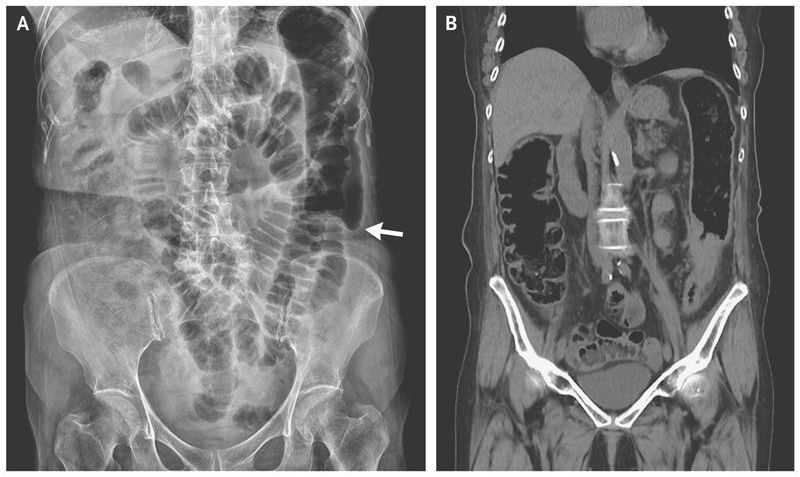

A 74-year-old woman presented to the emergency department with a 3-day history of lower abdominal pain, nausea, and vomiting. She had been unable to pass any stool for 1 week and reported having had small-caliber stool during the previous 6 months. On physical examination, bowel sounds were reduced, and the patient had periumbilical tenderness. Laboratory studies revealed normocytic anemia with a hemoglobin level of 9.6 g per deciliter (reference range, 12.3 to 15.3). A plain-film radiograph of the abdomen showed marked dilatation of bowel loops and abrupt termination of gas within the descending colon, referred to as a colon cutoff sign (Panel A, arrow). Computed tomography of the abdomen revealed segmental wall thickening of the descending colon (Panel B). Colonoscopy revealed a circumferential ulcerative lesion in the descending colon, and the results of pathological testing were consistent with adenocarcinoma of the colon. In this patient, the colon cutoff sign was caused by mechanical narrowing due to colon cancer. The colon cutoff sign is classically described in association with acute pancreatitis, when inflammation causes spasm or narrowing at the splenic flexure. The patient underwent hemicolectomy on the left side and received adjuvant chemotherapy. At follow-up 4 months after surgery, she had no evidence of local disease recurrence or distant metastases.